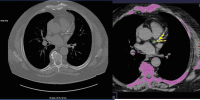

Abbildung 2: Nach dem Risiko-Score Hochrisikopatientin (75 Jahre, seit > 20 Jahren schlecht eingestellter DM und Hypertonus, BMI > 30; LDLc 130 mg/dl, TG 190 mg/dl, Z. n. zweimaliger Radiatio und Chemotherapie bei Neo. mammae). Mit diesem unauffälligen CCTA-Befund hat die Patientin eine exzellente kardiovaskuläre Langzeitprognose, profitiert sicher nicht von einer Primärprävention mit ASS oder einer Hochdosis-Statintherapie.